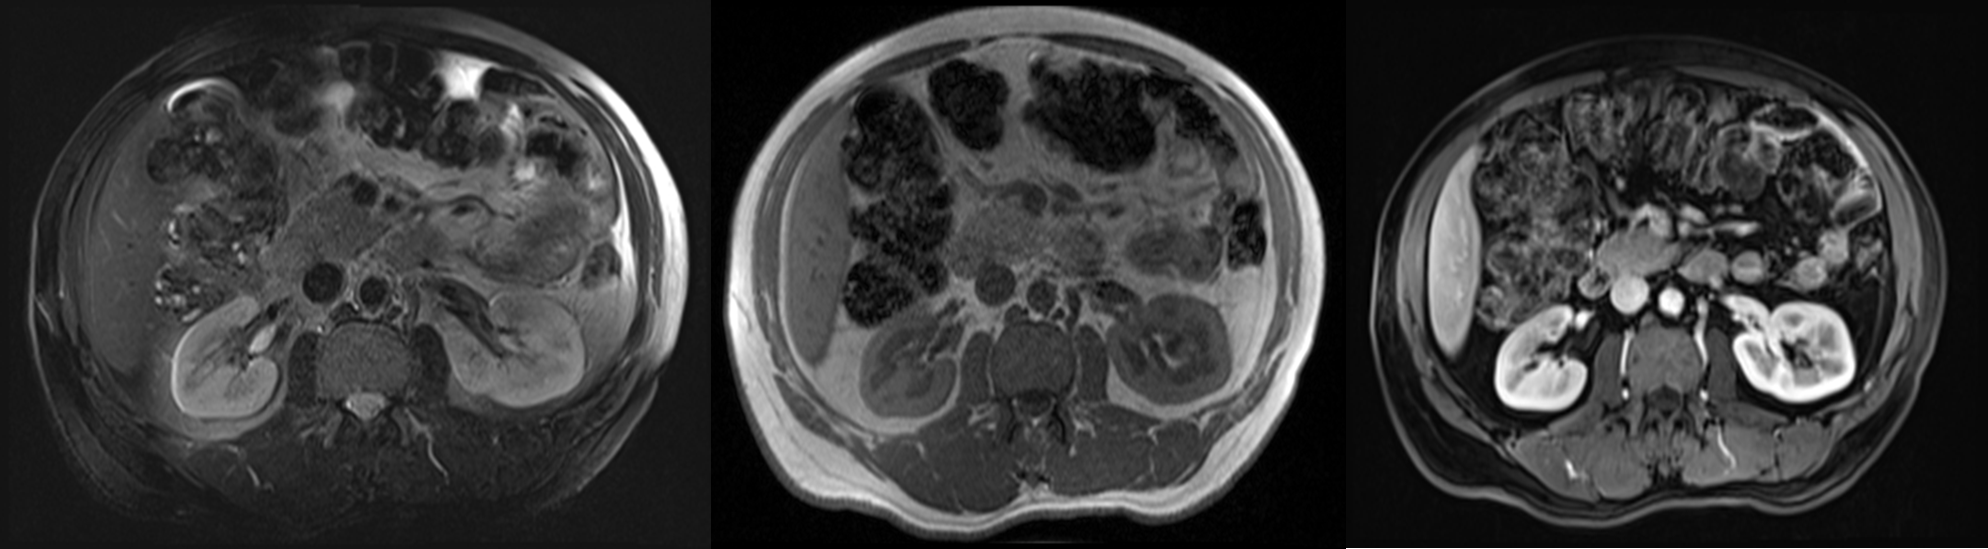

MRI gives similar anatomical information to CT, with the advantage of being able to obtain scans directly in multiple planes.

It is generally used in selected circumstances, e.g.:

- = To demonstrate renal artery stenosis or inferior vena caval extension of renal tumours,

- = To clarify problems not solved by ultrasound or CT.

- = To assess the extent of bladder or prostate cancer prior to consideration for surgery

Calcification is not visible on MRI, which is one of the main disadvantages of the technique for renal tract imaging.